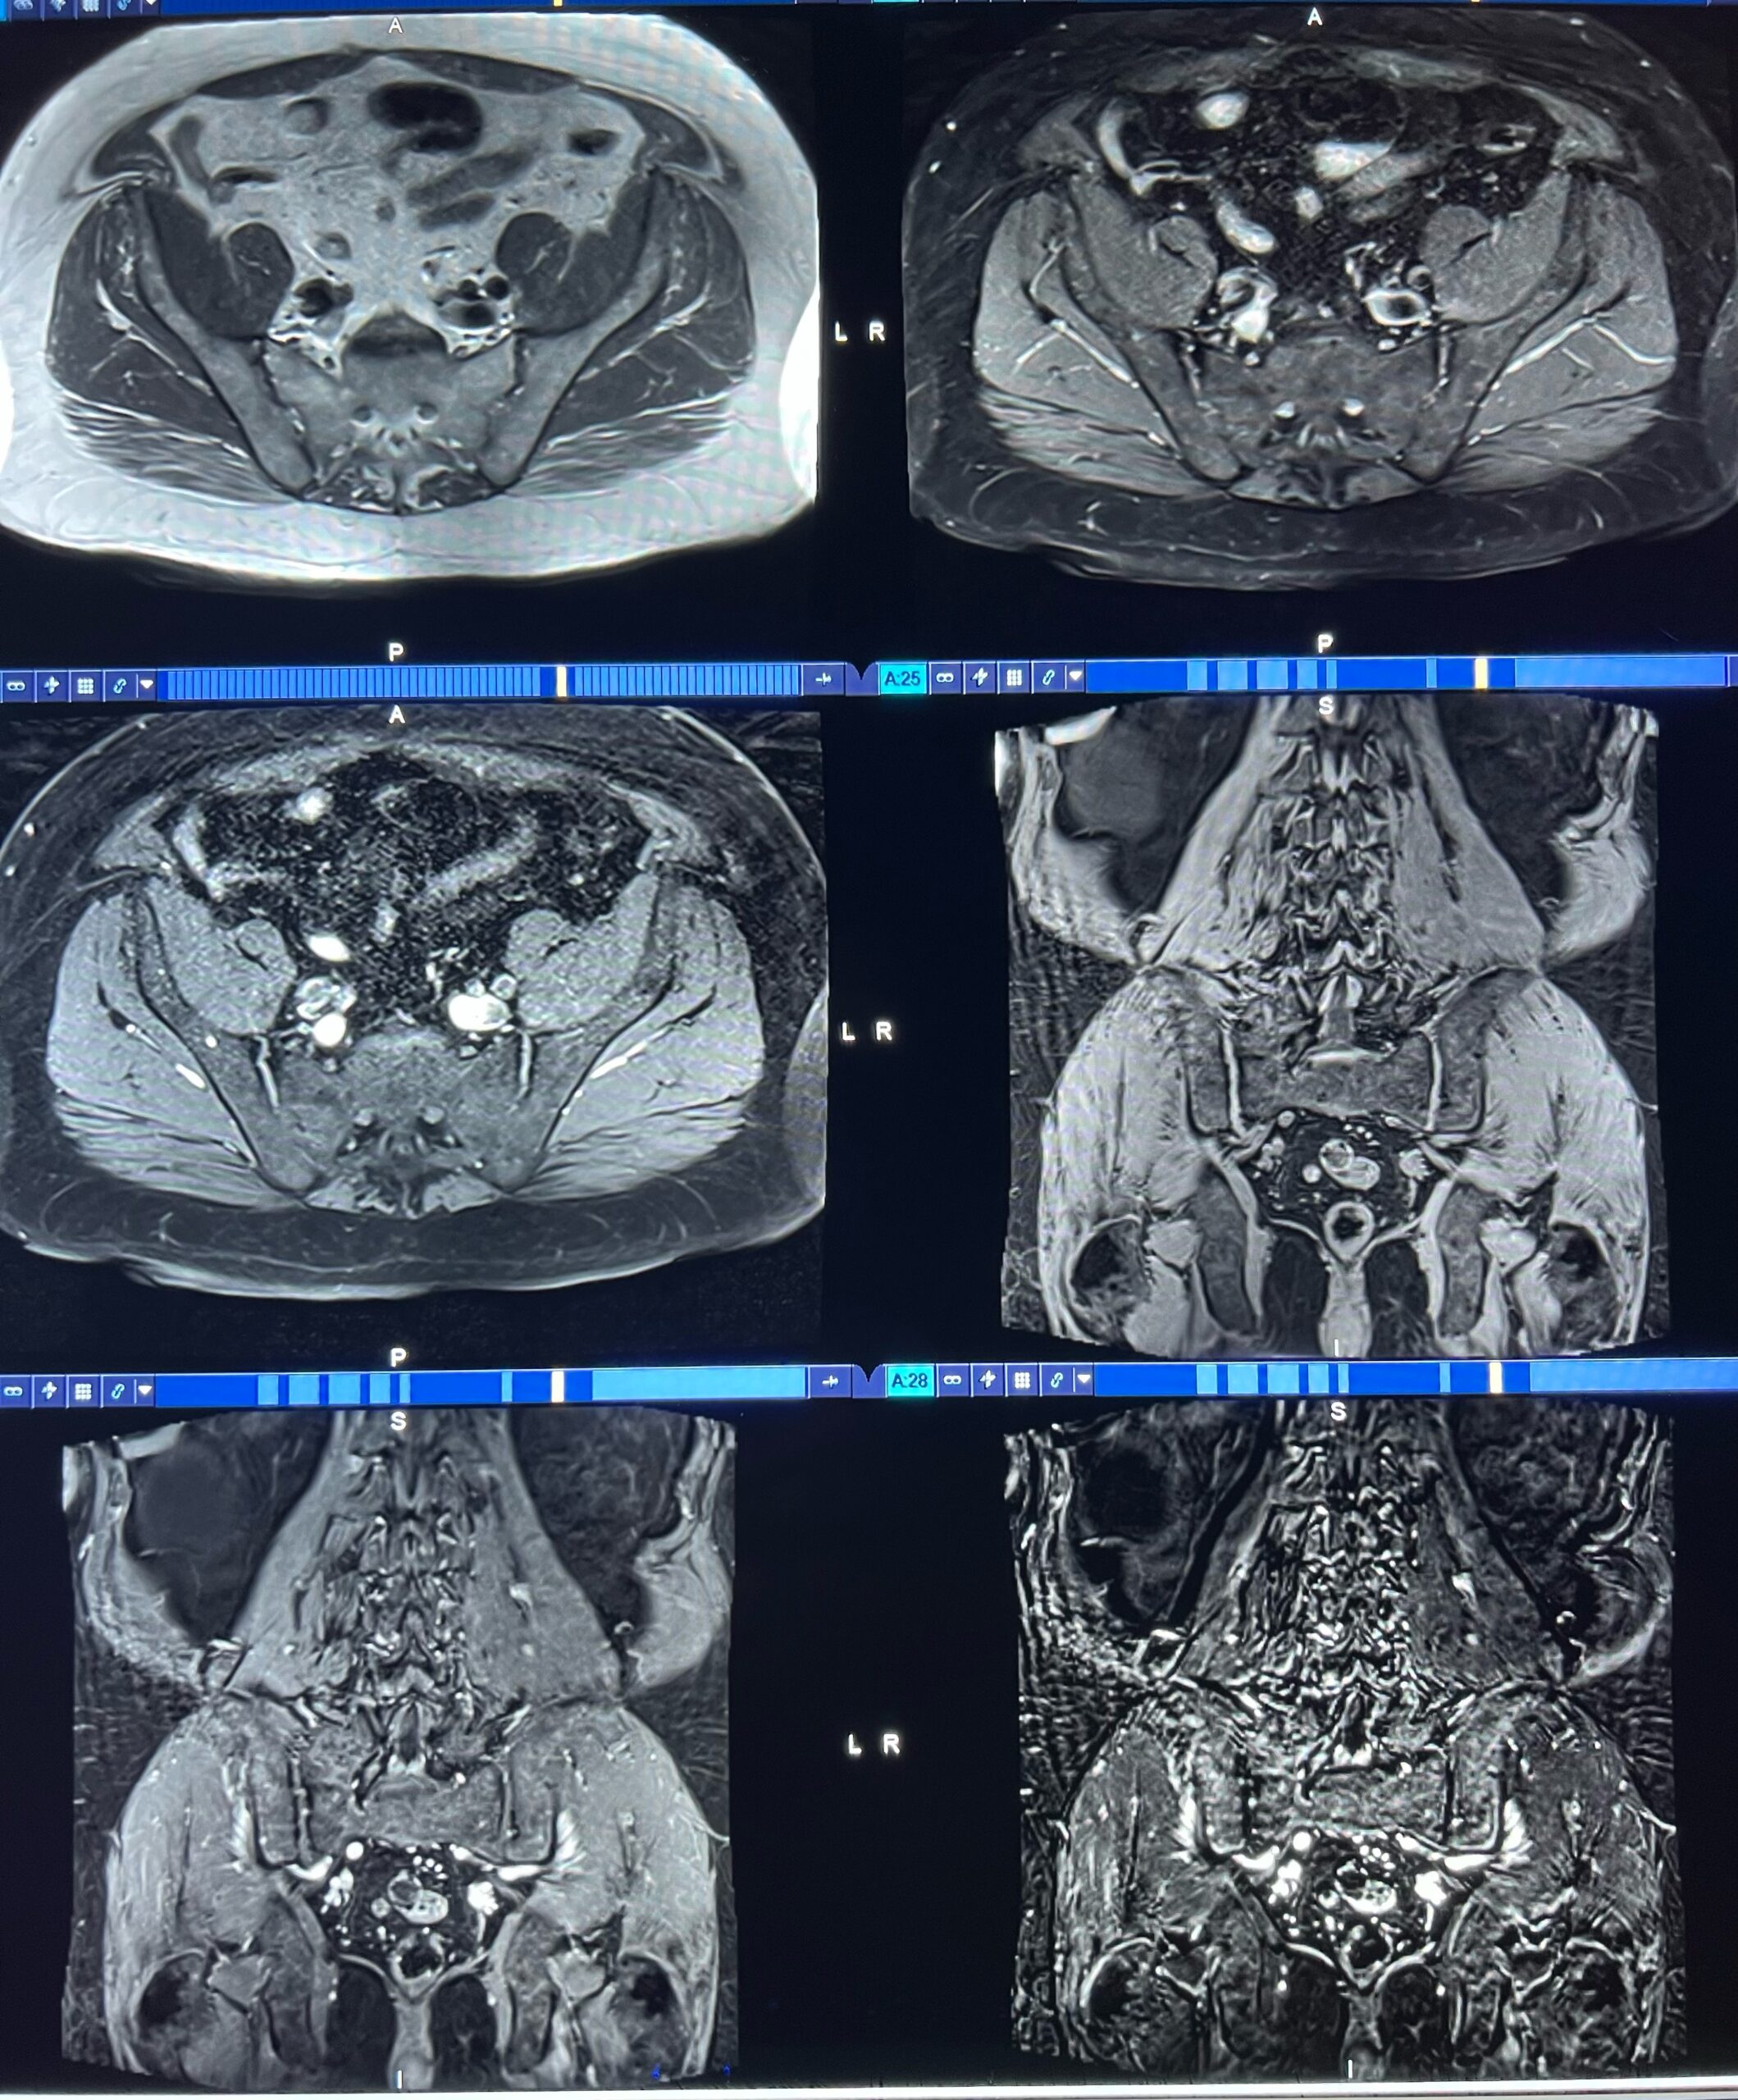

28M 10 years hip pain XR femoral head lesion and MRI, please help

Some were curious about the left hip MRI scout includes the left hip CAM morphology is bilateral, but there is nothing to suggest Legg Calve Perthes. There is no left femoral bone lesion. There is mild cartilage space narrowing on the right side only. On Mon, Jul 31, 2023 at 3:39 PM hilary umans <hilary.umans> wrote: […]